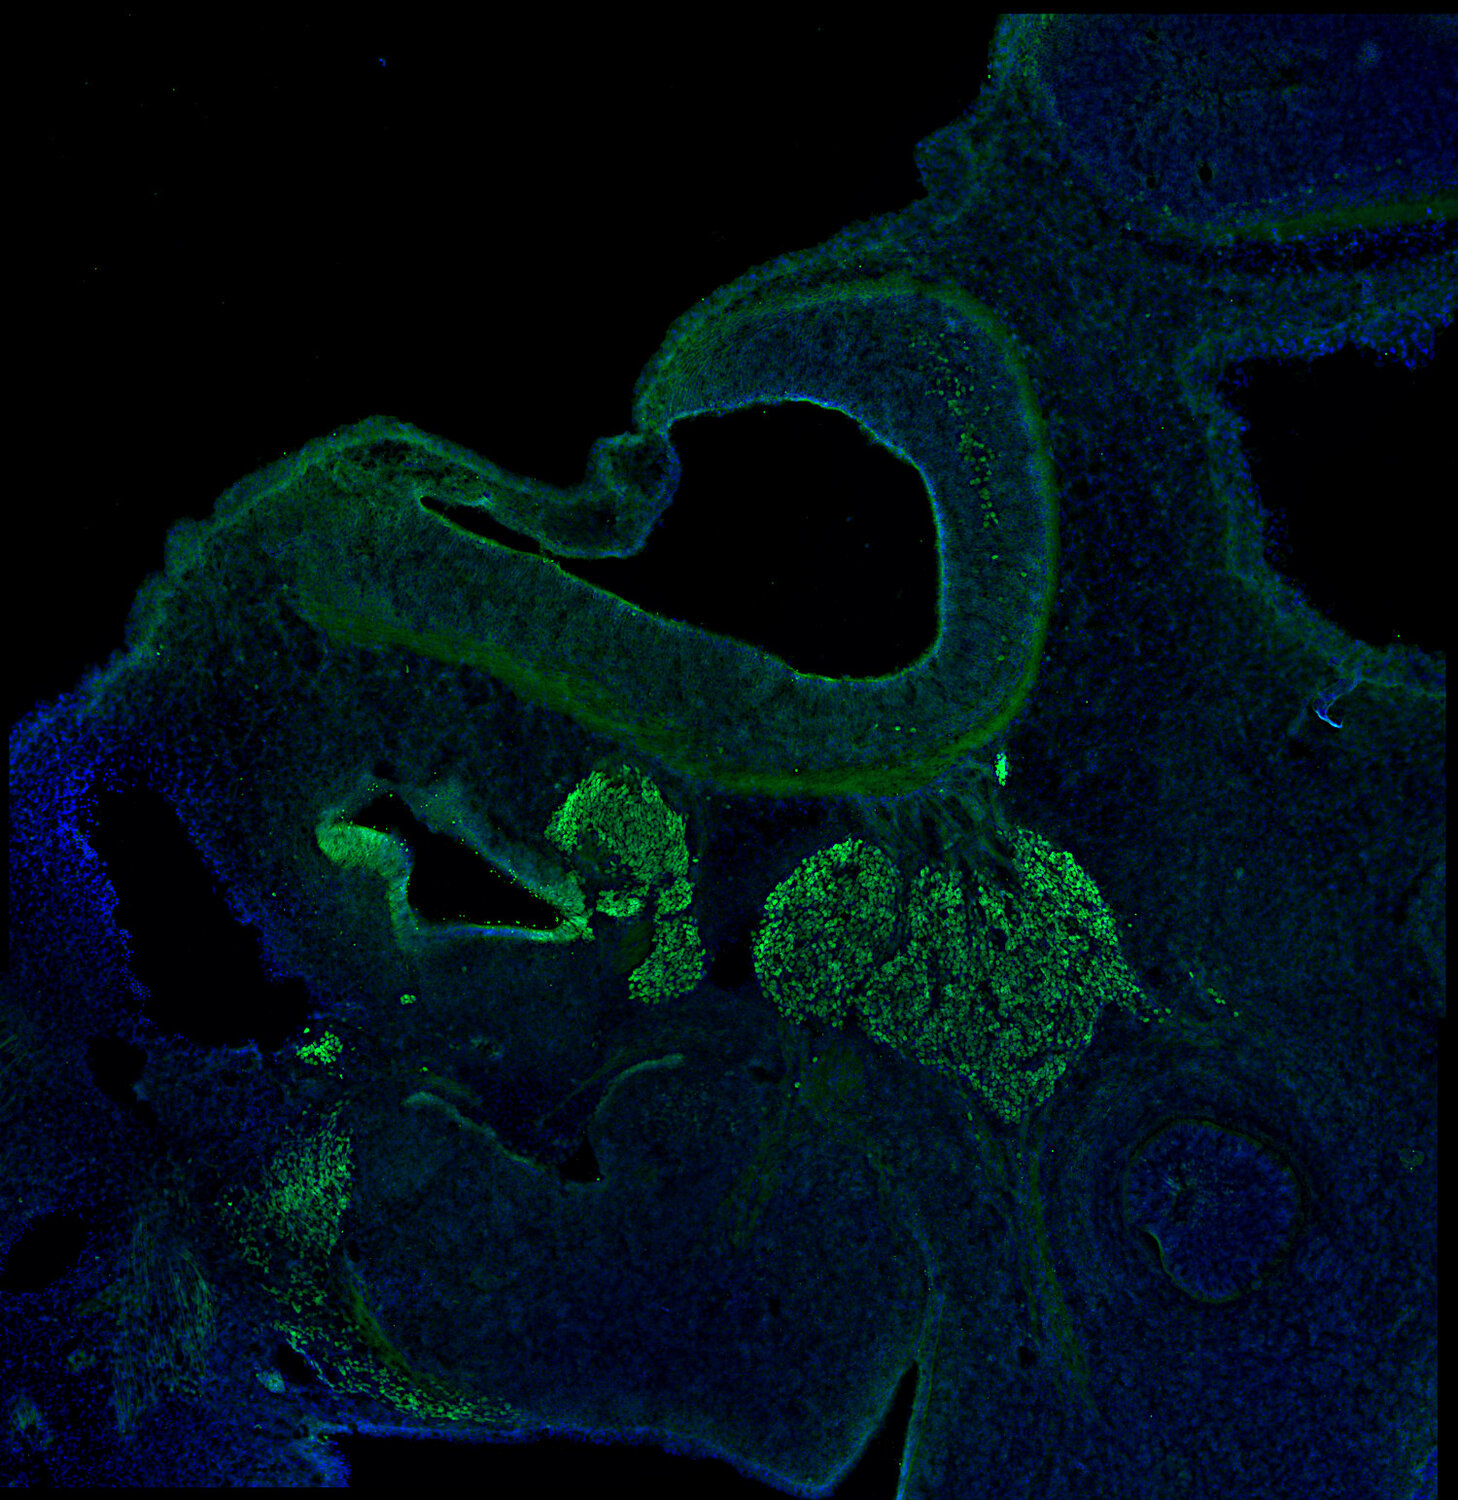

IHC: 1 : 100 (see remarks) gallery

IHC-P (FFPE): 1 : 200 up to 1 : 1000 gallery

IHC: For optimal results in retina tissue, follow the retina protocol.

Islet-1 (Isl1) is a member of the LIM/homeodomain family of transcription factors. It binds and regulates the promoters of the insulin, glucagon and somatostatin genes, and may play an important role in regulating insulin gene expression. It is central to the embryogenesis of pancreatic islets of Langerhans and is involved in the specification of motor neurons. It is expressed in subsets of neurons of the adrenal medulla and dorsal root ganglion, and in inner nuclear and ganglion cell layers in the retina.